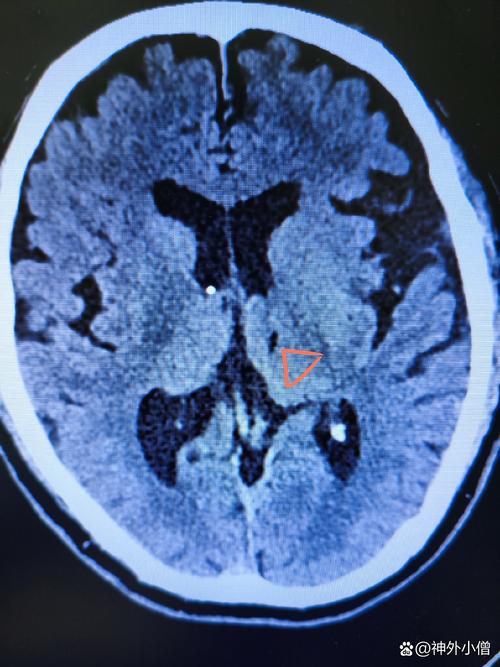

(图片来源网络,侵删)

关键在于区分“脑梗”本身和“脑梗的后果/原因”,陈旧性脑梗指的是发病时间超过数周甚至数月的脑梗死病灶,这个病灶本身(已经坏死的脑组织)是无法通过手术“复活”的,围绕陈旧性脑梗,有两类主要的手术情况: